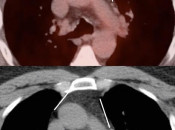

3. Chest

- Inflammatory Lymph Nodes

- Thymic Rebound

- Pleura: Talc Pleurodesis vs. Malignancy vs. Inflammation

-

Radiation-Induced Lung Disease

- Radiation Pneumonitis

- Radiation Fibrosis

- "Post-Therapeutic Inflammatory Changes" / Scarring of the Lung